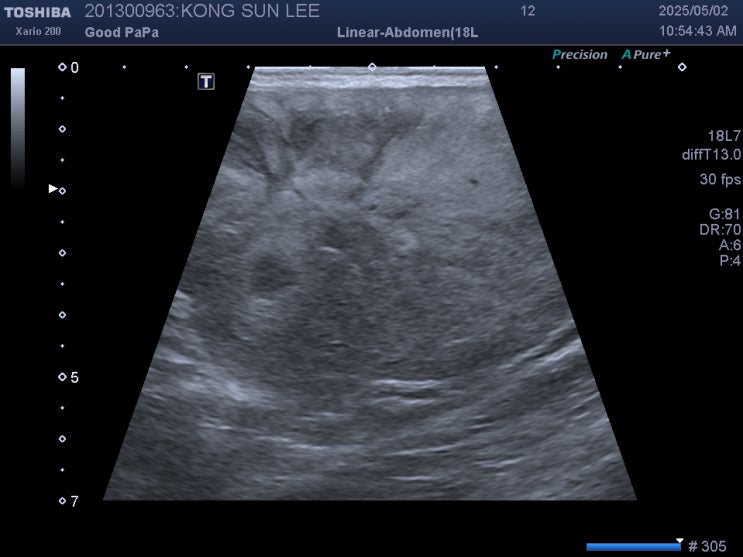

13살 푸들 강아지 간종양 관리 / 반려견 종양에 의한 빈혈 치료 / 애완견 간종양 증상은? / 강아지 빈혈 원인, 이유, 증상 / 강아지 빈혈은 꼭 수혈해야 하나요.?

안녕하세요~ 굿파파 수의사입니다. 오전부터 내린 비가 멈추었네요~ 일교차가 심해서 감기 걸리기 딱 좋은 ...